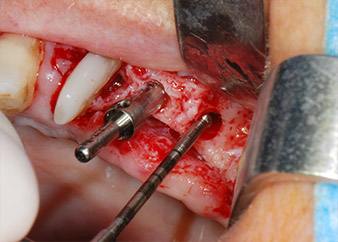

Implant beds were prepared at sites 25 and 26 with rotary instruments, used in a contra-angle handpiece with a 20 : 1 transmission ratio with an updated powerful implant motor (Implantmed, W&H) (Fig. 8).

The final preparation next to the sinus was again carried out with a piezoelectric instrument (Piezomed, insert S2).

implant motor

Fig. 8: Rotary preparation of the implant bed short of the floor of the maxillary sinus at position 25, carried out with an updated implant motor.